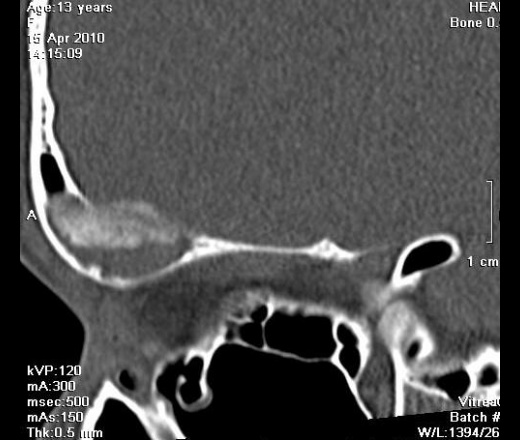

Девочка, 13 лет. К сожалению анамнеза толком не знаю, девочку не видела, снимали без меня. Основная жалоба на наличие "шишки". В направлении - исключить объемный процесс. Написала, что вероятнее всего фиброзная дисплазия. При несоответсвии клиническим данным рекомендуется биопсия. А сомнения остались. Как вы считаете что это может быть?

Вряд ли это псевдотумор. Мягкие ткани орбиты не изменены. Все в пределах кости. Кость вздута. Гемангиома - это вариант, на мой взгляд.

Шишка по верхнему краю орбиты.

Но, тут, ведь два патологических процесса - один в лобной пазухе, другой - в орбите?

Это "объём" в орбите?

Это нижний полюс "образования". Шишка похоже не связана с пазухой, а в орбиту вдается за счет вздутия кости. Завтра постараюсь выложить еще коронарных срезов.

Коронарные срезы.

Да я на первое место поставила фиброзную дисплазию. И порекомендовала биопсию при несоответствии клиническим данным. Надеюсь не ошиблась.

Жалко, что Вы девочку не видели, есть синдром Олбрайта, изменения идут не только костные, но и идет преждевременное половое созревание, так же наличие пегментных пятен. Возможно фиброзная дисплазия орбиты, только не приближена к классике.

Фиброзная дисплазия с обструкцией дренажа фронтального синуса. Интересное наблюдение. По синдрому Олбрайта - согласен с коллегой v1tal, ещё характерен невысокий рост (гипостатура).

Мой грех, девочку упустила. Спасибо, Марио, за ссылки. Правда очень похоже на фиброзную дисплазию.

Типичное место локализации метастаза нейробластомы у детей. Нужно обследовать брюшную полость и забрюшинное пространство